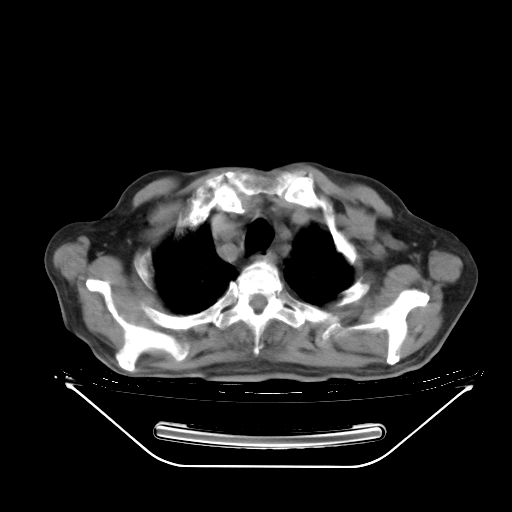

胸腹部CT,诊断意见:左上肺叶钙化灶、左侧胸膜局限性增厚并钙化、胆囊炎。描述部分肺组织呈磨玻璃样改变。